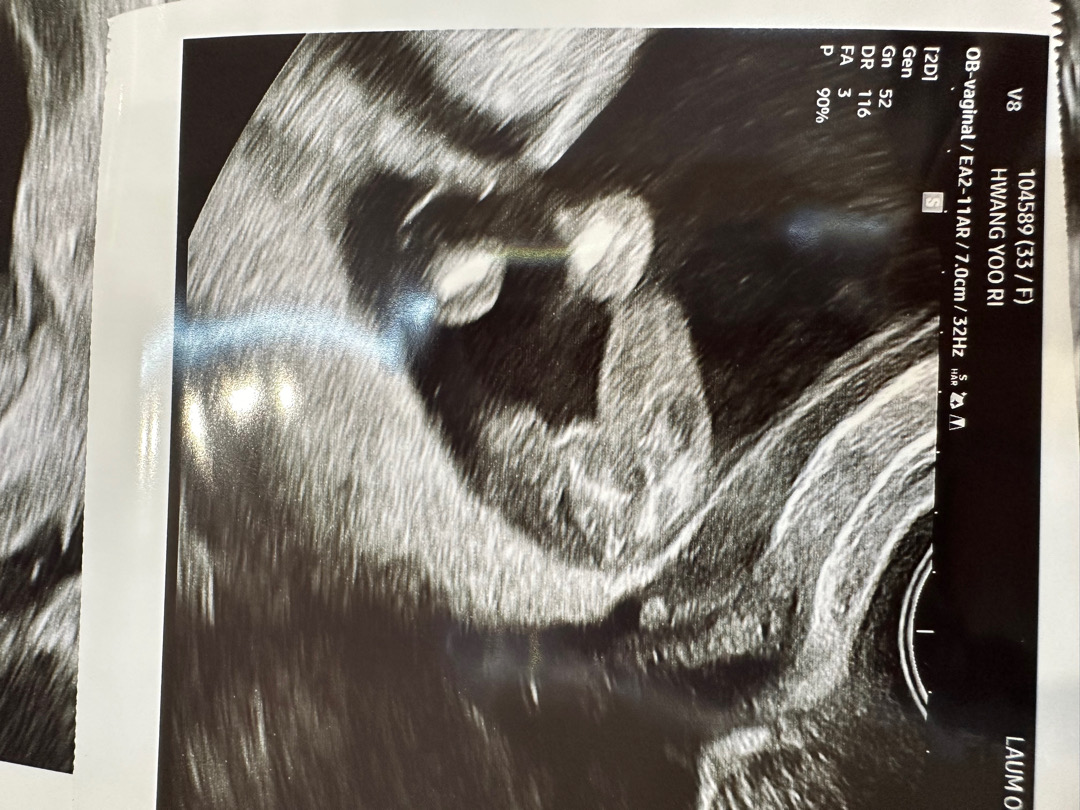

각도법이 정말 어느정도 맞는걸까요ㅎㅎ 다음주에 해외가기전에 건강여부 여쮸ㅓ볼겸 산부인과 방문했다가 성별알아왔어요 ! ㅎㅎ 14주1일차 딸 당첨입니당😆